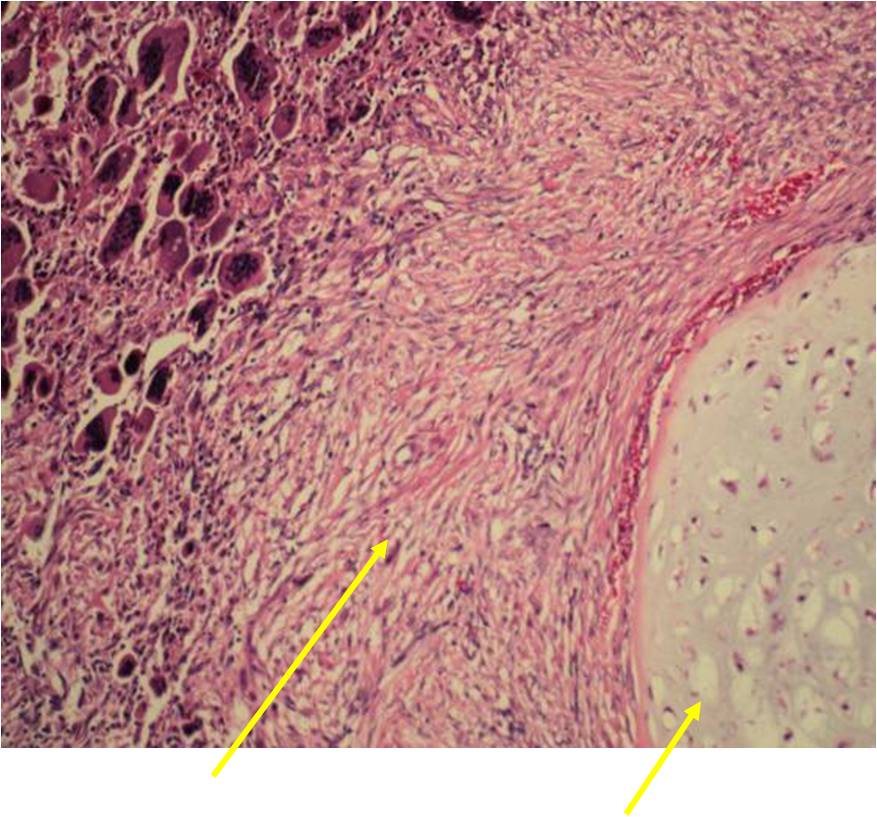

Microscopic Pathology

- Chondrosarcoma component is often grade I (Low Grade Hyaline Type Cartilage)

- Dedifferentiated component

- Predominant noncartilaginous/spindle sarcoma component varies

- Fibrosarcoma and MFH most frequently reported

- MFH is a high grade pleomorphic spindle cell tumor with a storiform pattern

- Osteosarcoma is third most common dedifferentiated component

- Rhabdomyosarcoma and angiosarcoma also reported

Junction of cartilaginous and noncartilaginous components is sharp and distinct. There are no dedifferentiated areas admixed in the middle of the cartilaginous areas

(Top Arrow) High Grade Dedifferentiated Spindle Cell Sarcoma Component

(Left Arrow) Low Grade Cartilage Component

(Right Arrow) Low Grade Cartilage Component